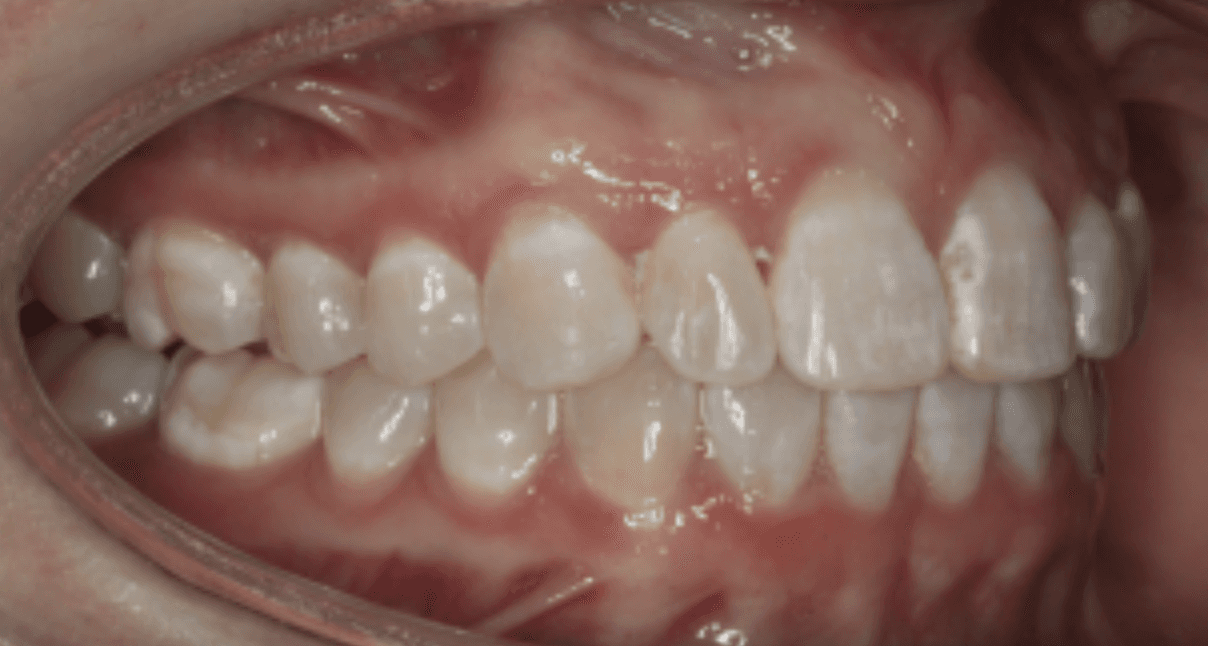

Diagnosis: Deep bite, lower anterior crowding, rotated upper lateral, arch misalignment, wear on teeth from grinding

Adjuncts: Attachments, IPR

Initial treatment

INTRAORAL